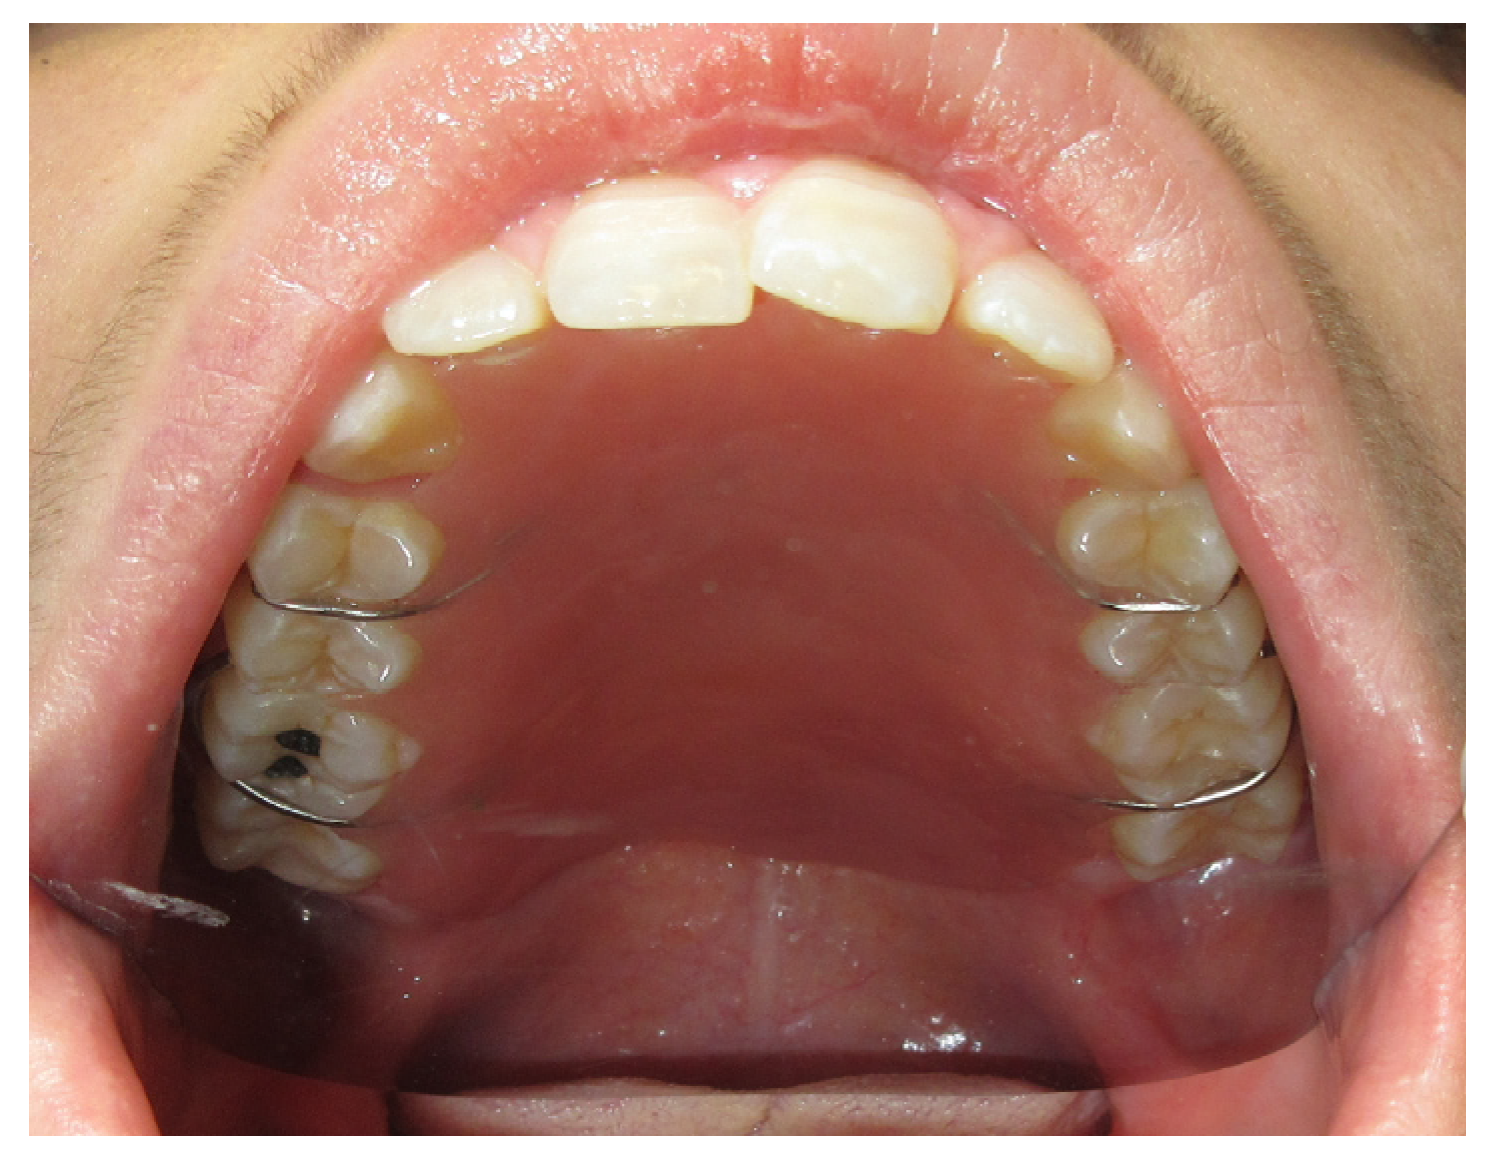

3.1.2. Case 2: P.S.

| P.S. | X | * | 7 | 0 | ||